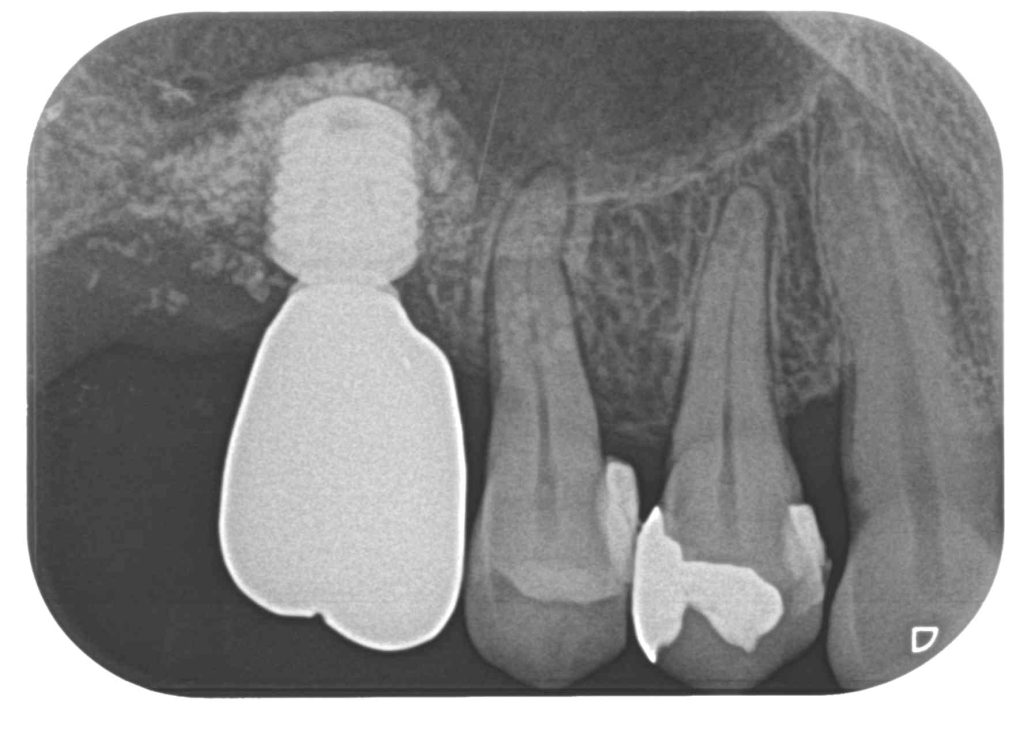

症例470代 女性 主訴 右奥歯がグラグラして噛めない

治療前

治療後

治療前

治療後

右上小・大臼歯部は、残存骨が1~2㎜程度しかないので、ソケットリフト(上顎洞洞底膜挙上術)を適用。

約5ヶ月間の治療期間を経て、ジルコニアを装着し終了。

リスクとしては外科的侵襲がある。デメリットは、保険外診療の為、経済的負担がある。

費用 126万(税込)(オペ・仮歯・最終補綴物まで含む)